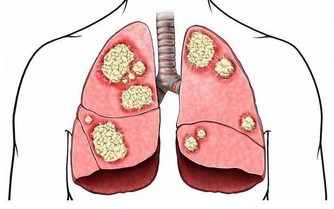

不分種族不分性別不分年齡,任何人都可能患上關節病。 關節病可以是膝關節直接受到衝擊或扭傷,也可以是關節骨和軟骨部分磨損、撕裂而引起。 炎症性關節病還可以由風濕性疾病引起,比如風濕性關節炎或系統性紅斑狼瘡,這些疾病導致的關節腫脹對關節的損傷是永久性的。

是軟骨磨損導致的關節病,主要表現為關節疼痛,稍活動後減輕,過度活動後又加重。治療是吃非甾體類抗炎藥、鍛鍊和減肥,一般不用手術治療。 但風濕性關節炎患者的關節軟骨破壞較嚴重的,需要做膝關節置換術。